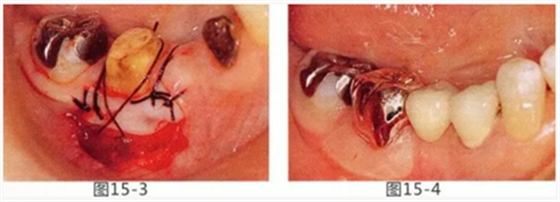

圖15-1,2 右下6近中部的頰系帶延伸到游離齦,附著齦也處于缺失狀態(tài)。如果在這個狀態(tài)下進行修復(fù),會使清潔變得困難,容易引發(fā)牙齦萎縮。

圖15-3 切除系帶。為了獲得附著齦,進行游離齦移植。

圖15-4 手術(shù)完成6個月后,佩戴修復(fù)體時的狀態(tài)。